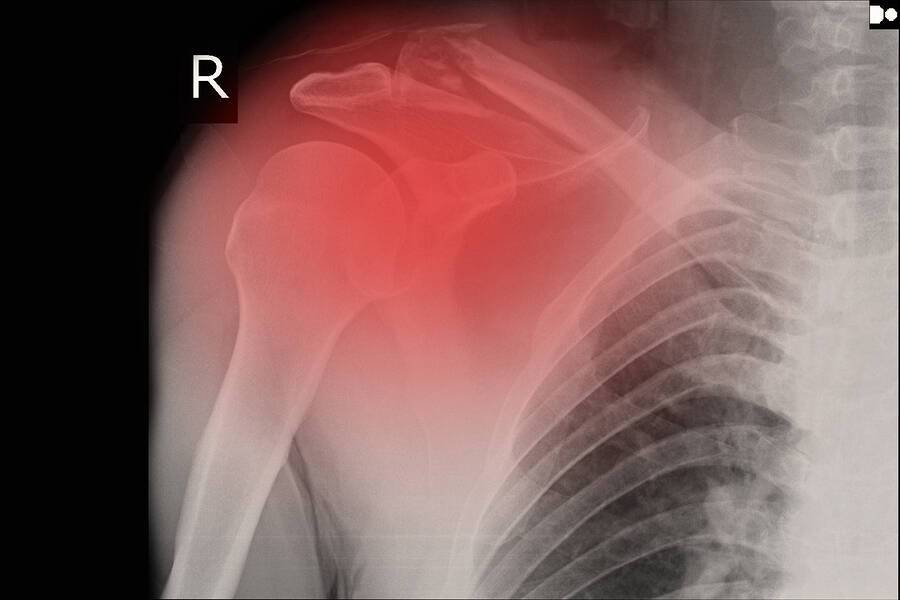

Рентген плеча: примеры снимков и их расшифровка